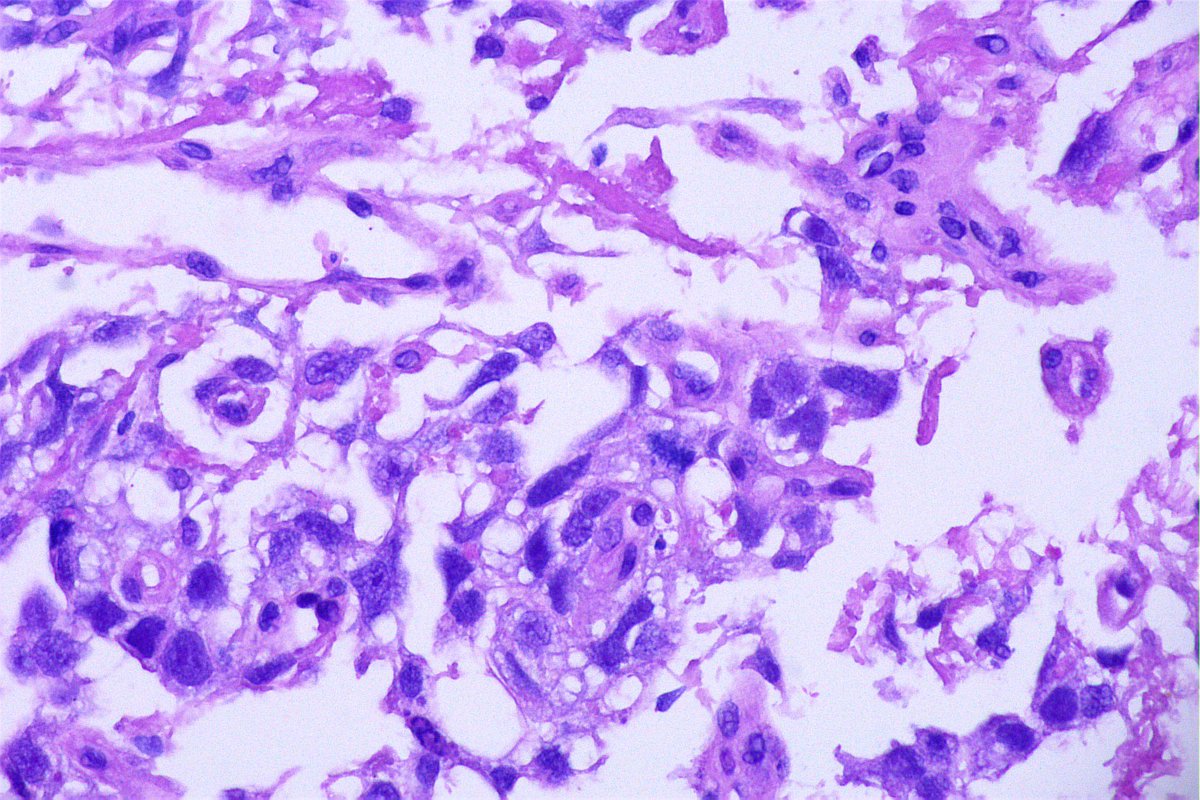

Case of the day. M, 30 years old, with weight loss, pulmonary consolidation area, mediastinal lymph node enlargement, and endobronchial polypoid lesions. Bronchial biopsy performed. #pulmpath #pathology